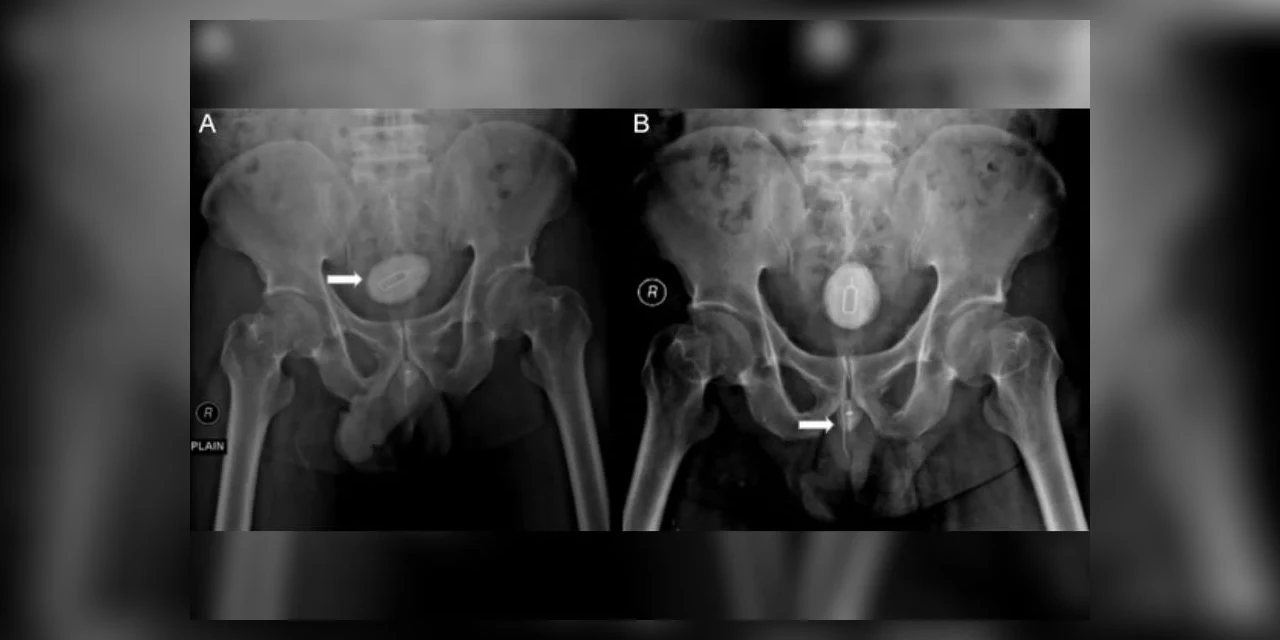

Foto: Divulgação/Hospital Acadêmico Geral Soetomo

Um homem de 48 anos, da Indonésia, precisou passar por uma cirurgia após enfiar uma chave para retirar chip de celular, um cabo elétrico e um elástico no próprio pênis. O paciente esperou seis meses antes de procurar atendimento médico e só buscou ajuda após começar a sentir muita dificuldade para urinar. Segundo o relato de caso publicado na revista médica Radiology Case Reports, apesar da atitude surpreendente, ele não tinha diagnóstico de problema mental. A radiografia da pelve do paciente mostrou um objeto opaco e uma “sombra” semelhante a um fio. Os médicos disseram que o objeto de metal levou o corpo a desenvolver uma espécie de pedra na bexiga do paciente.